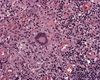

Describe la imagen y el diagnóstico

Es un cultivo de Mycobacterium tuberculosis demostrando el bacilo acido-alcohol-resistente.